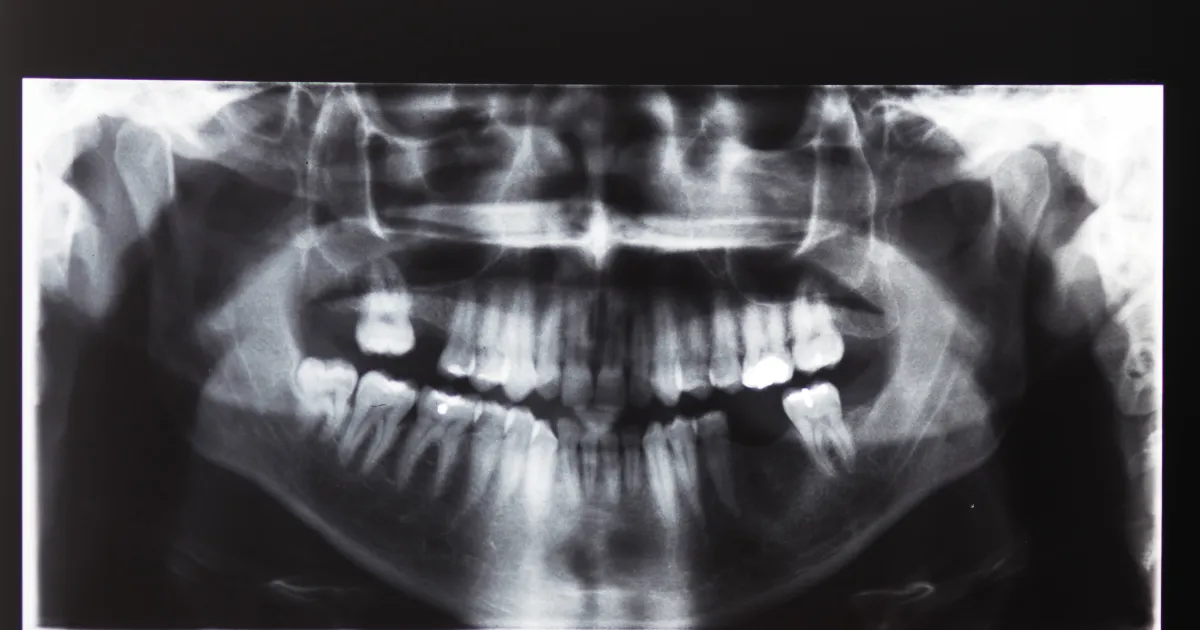

親知らずが生える際に、顎の大きさであったり歯列のスペースが十分に確保されていないと手前の歯が押し出され、歯並びや噛み合わせが悪くなる原因となってきます。

特に横向きや斜めに生えることが多い親知らずは、周りの歯に圧力をかけ、徐々にではありますが前歯や奥歯の位置をずらしてしまうこともあります。

親知らずが横向きや斜めに生えている

親知らずが横向きや斜めに生えることは、スペースの不足が原因です。

この異常な位置は、他の歯を押し出したり、歯列を歪ませる原因となるため、他の歯の健康に悪影響を及ぼします。